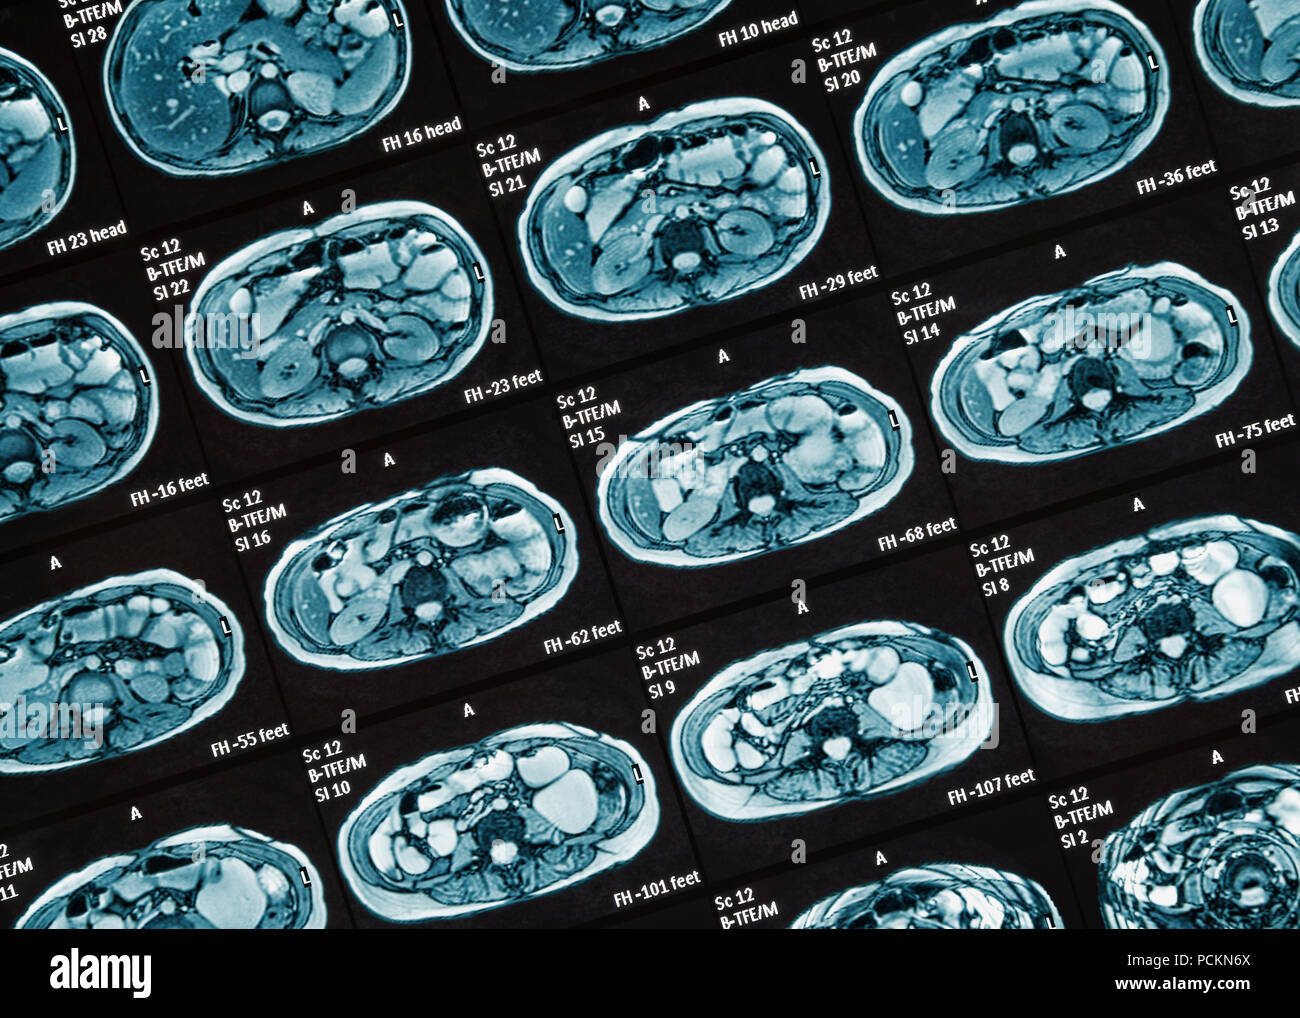

MRI Scan, Close Up. MR Enterography of the small intestine a noninvasive medical test used to diagnose medical conditions of the bowels, like Crohn's Stock Photohttps://www.alamy.com/image-license-details/?v=1https://www.alamy.com/mri-scan-close-up-mr-enterography-of-the-small-intestine-a-noninvasive-medical-test-used-to-diagnose-medical-conditions-of-the-bowels-like-crohns-image214334034.html

MRI Scan, Close Up. MR Enterography of the small intestine a noninvasive medical test used to diagnose medical conditions of the bowels, like Crohn's Stock Photohttps://www.alamy.com/image-license-details/?v=1https://www.alamy.com/mri-scan-close-up-mr-enterography-of-the-small-intestine-a-noninvasive-medical-test-used-to-diagnose-medical-conditions-of-the-bowels-like-crohns-image214334034.htmlRFPCKN6X–MRI Scan, Close Up. MR Enterography of the small intestine a noninvasive medical test used to diagnose medical conditions of the bowels, like Crohn's